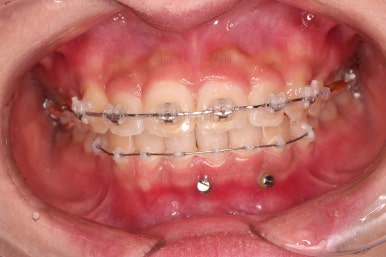

우선 윗니 앞니는 장치를 부착했고요.

아래 앞니는 장치 부착 이전에 아래로 앞니를 내려줄 미니스크류를 식립했습니다.

미니스크류가 단단하게 붙었을 시점에 아래 앞니도 장치를 부착하고요.

과개교합 개선을 위해서 미니스크류까지 힘을 줘서 아래 앞니를 내려줍니다.

이번 환자분이 사용한 장치는 엠파워 클리어라고 하는 자가결찰 세라믹 장치입니다.

일반적으로 클리피씨라고 많이 알고 계시는 장치가 "자가결찰 세라믹" 종류이며 여러 종류 중 엠파워 클리어도 있습니다.

제조사만 일본(클리피)이냐 미국(엠파워)이냐의 차이입니다.

아래 앞니는 브라켓보다는 훨씬 작은 미니튜브 장치를 사용했습니다.

과개교합의 경우 브라켓을 부착하게 되면 씹히게 되어 치료과정이 수월하지 못하기 때문이죠.

장치 부착 시점의 장치가 보이는 모습과 입매 변화 관찰해 주시고요.